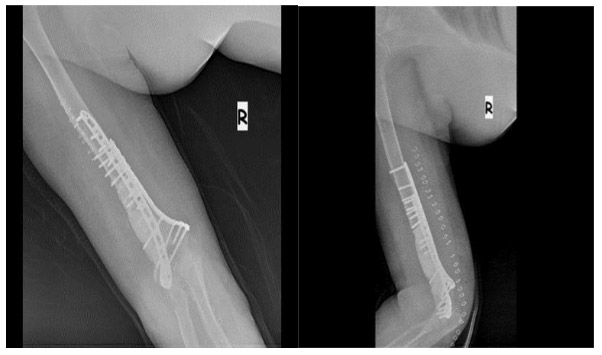

Post-surgery: The X-ray shows that after the tumor was removed, the resulting cavity was filled with bone cement and reinforced with two titanium plates.